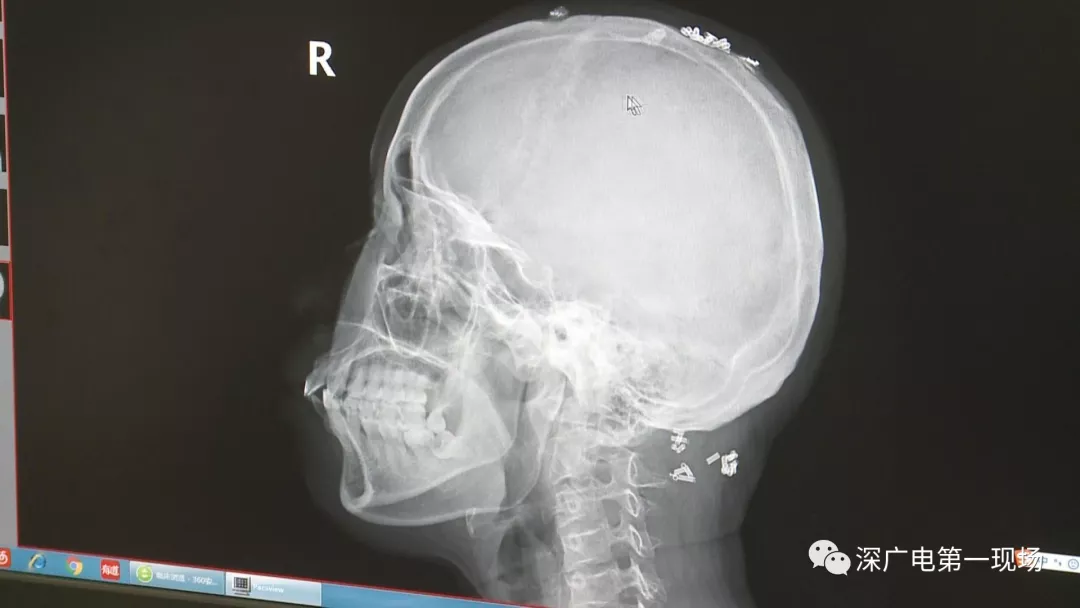

彈簧圈已“寄生”三年

部分形成包塊難以取出

據(jù)了解,這位患者周身的彈簧圈已經(jīng)固定了三年多,因?yàn)榛颊吒杏X治療效果不好,就來深圳求醫(yī)。